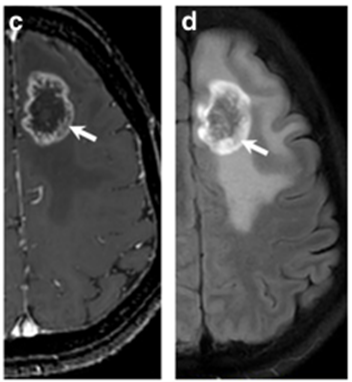

Những thay đổi tín hiệu MRI trong hoại tử do bức xạ không thể phân biệt được với những thay đổi liên quan đến khối u. Tuy nhiên, có một số đặc điểm hình ảnh đã được xác định có lợi cho chẩn đoán hoại tử não do xạ trị. Bao gồm:

- Tổn thương tăng tín hiệu hình vòng nhẫn trên nền khối u được điều trị và phù não xung quanh - Tổn thương tăng tín hiệu dạng nốt mới biểu hiện hình bong bóng xà phòng hoặc hình pho mát Thụy Sĩ - Tổn thương chất trắng có diện tích lớn hơn tổn thương chất xám. Tổn thương tín hiệu cao ở chất trắng quanh não thất trên T2 - Thương số tổn thương (Leision quotient- LQ) là tỷ lệ diện tích cắt ngang (CSA) tối đa của tổn thương khi nhìn thấy trên T2WI và CSA của tổn thương tăng tín hiêu khi nhìn thấy trên T1WI tiêm thuốc, LQ ≤0,3: gợi ý khả năng cao hoại tử não do bức xạ.

Hình 3: Hình ảnh tổn thương hoại tử não sau xạ trị trên phim chụp cộng hưởng từ. Tổn thương tăng tín hiệu hình vòng nhẫn (hình mũi tên) trên nền khối u được điều trị và phù não xung quanh